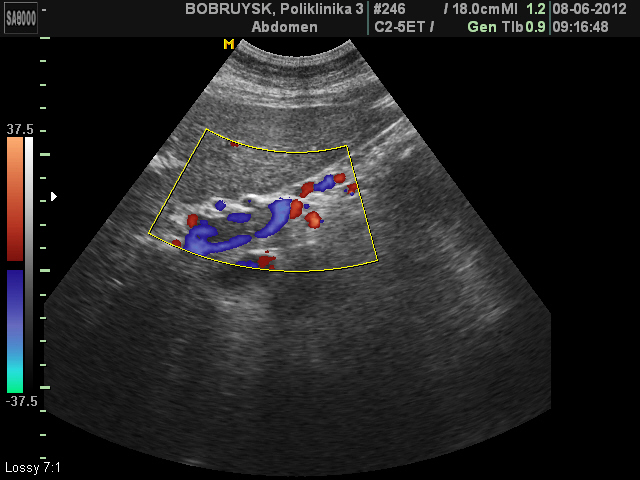

Тромбоз правой и левой ветвей воротной вены